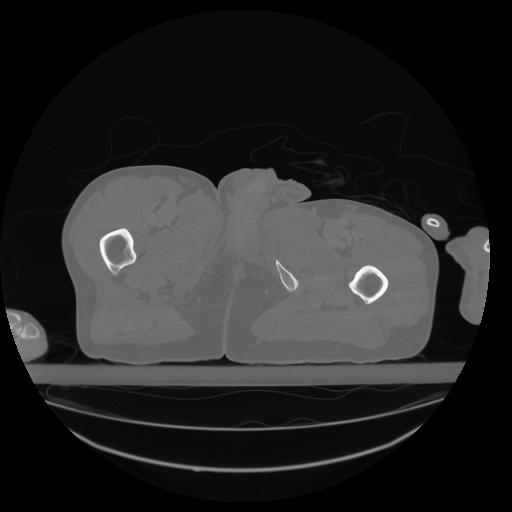

34 CUERPO,CE,Vol,1.0,CUERPO,,